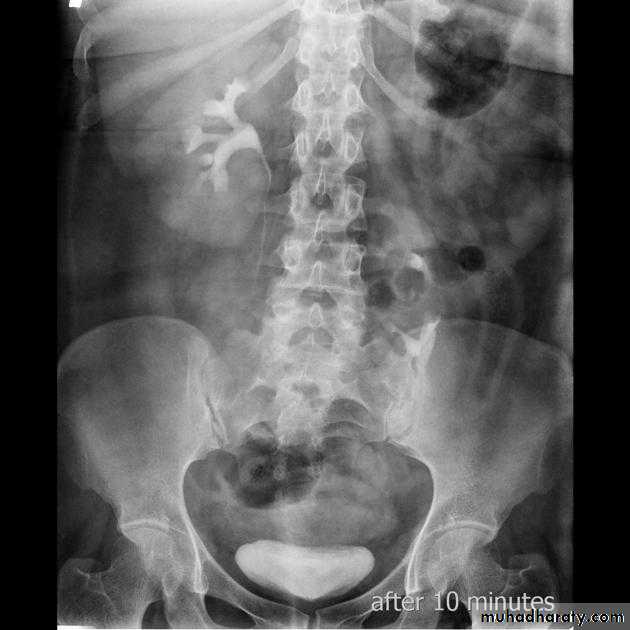

Normal IVU

Pelvi-ureteric junction obstructionFilling defects